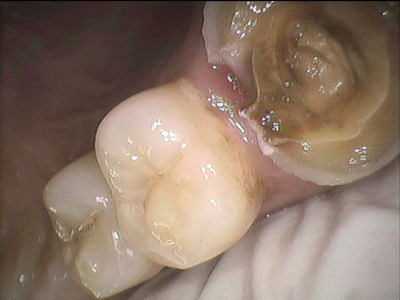

右奥上の奥歯から2番目の大きな歯にこんなかぶせ物が昨日まで私の口の中に入っていました。

そして、いよいよ昨日

まず最初の「金属アレルギー除去治療」がはじまりました。

記憶にあるのは

23歳くらいの頃です。たしか。

これが私の口の中に入っていた

歯科金属です。

もちろん保険で治療してもらったものです。

銀が錆びてます。

かぶせ物を外したところです。

私の口に入っていた保険の歯科金属です。

これは表面

こちらは削った歯に接着している側です。

心棒がセットでくっついているかぶせ物でした。

金属パラジウム

でした。

通称「金パラ」

これは歯科先進国ドイツでは

妊婦さんや子供には使用しないようにと

勧告を出しています。